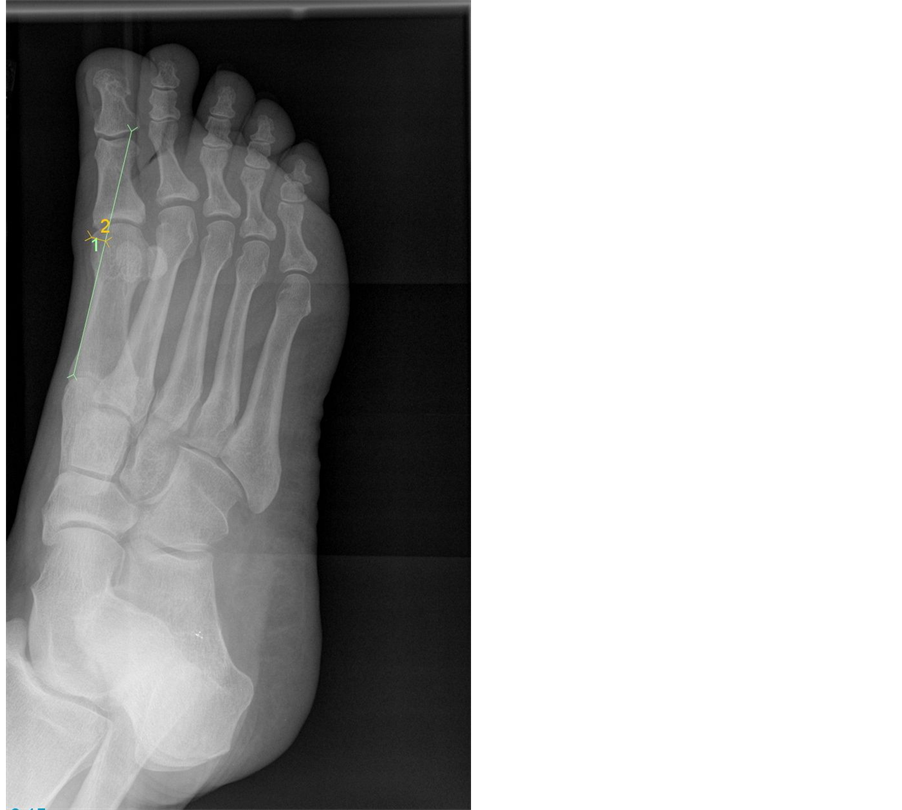

From www.researchgate.net

Preoperative Xray of the left foot showing medial deviation of Medial Eminence Toe Hallux valgus, commonly referred to as a bunion, is a complex valgus deformity of the first ray that can cause medial big toe pain and. As these authors argue, surgeons may resect the medial eminence to facilitate other bunion procedures, prevent potential complications. Halluces valgi) is a fixed abduction of the first metatarsophalangeal joint of the great toe. Characterized by. Medial Eminence Toe.